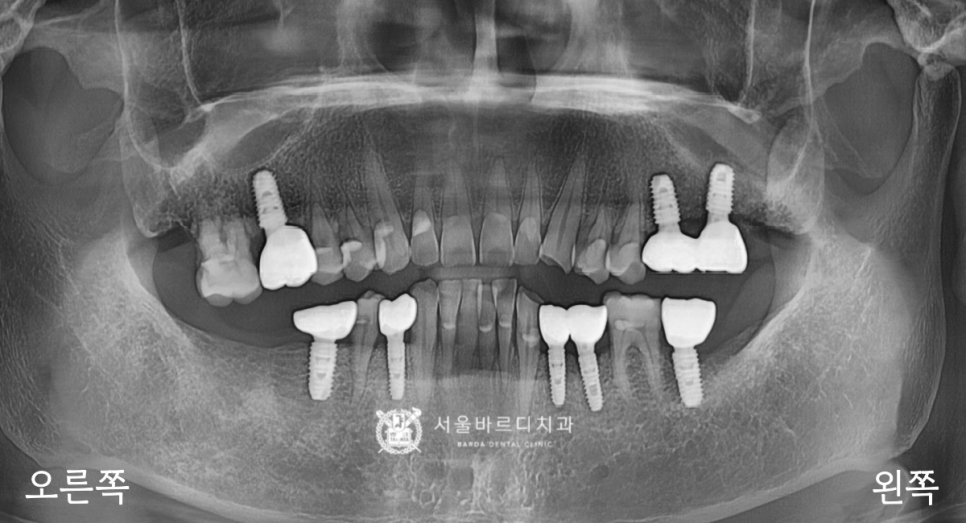

전반적인 뼈와 치아 상태를 확인하는

파노라마 엑스레이를 촬영하여 보니

기존에 이를 뽑은 자리가 많이 있었고,

오른쪽 위아래에 뿌리만 남은 부위가 있었습니다.

위와 같은 과정을 통해 보철을 모두 넣어드리고,

전반적으로 확인하기 위한 파노라마를 촬영했습니다.

위아래 높낮이에 잘 맞춰서 제작해 드린 덕분에

딱딱 부딪힐 때도 걸리는 부분이 없이

편안하다고 말씀하셨는데요.